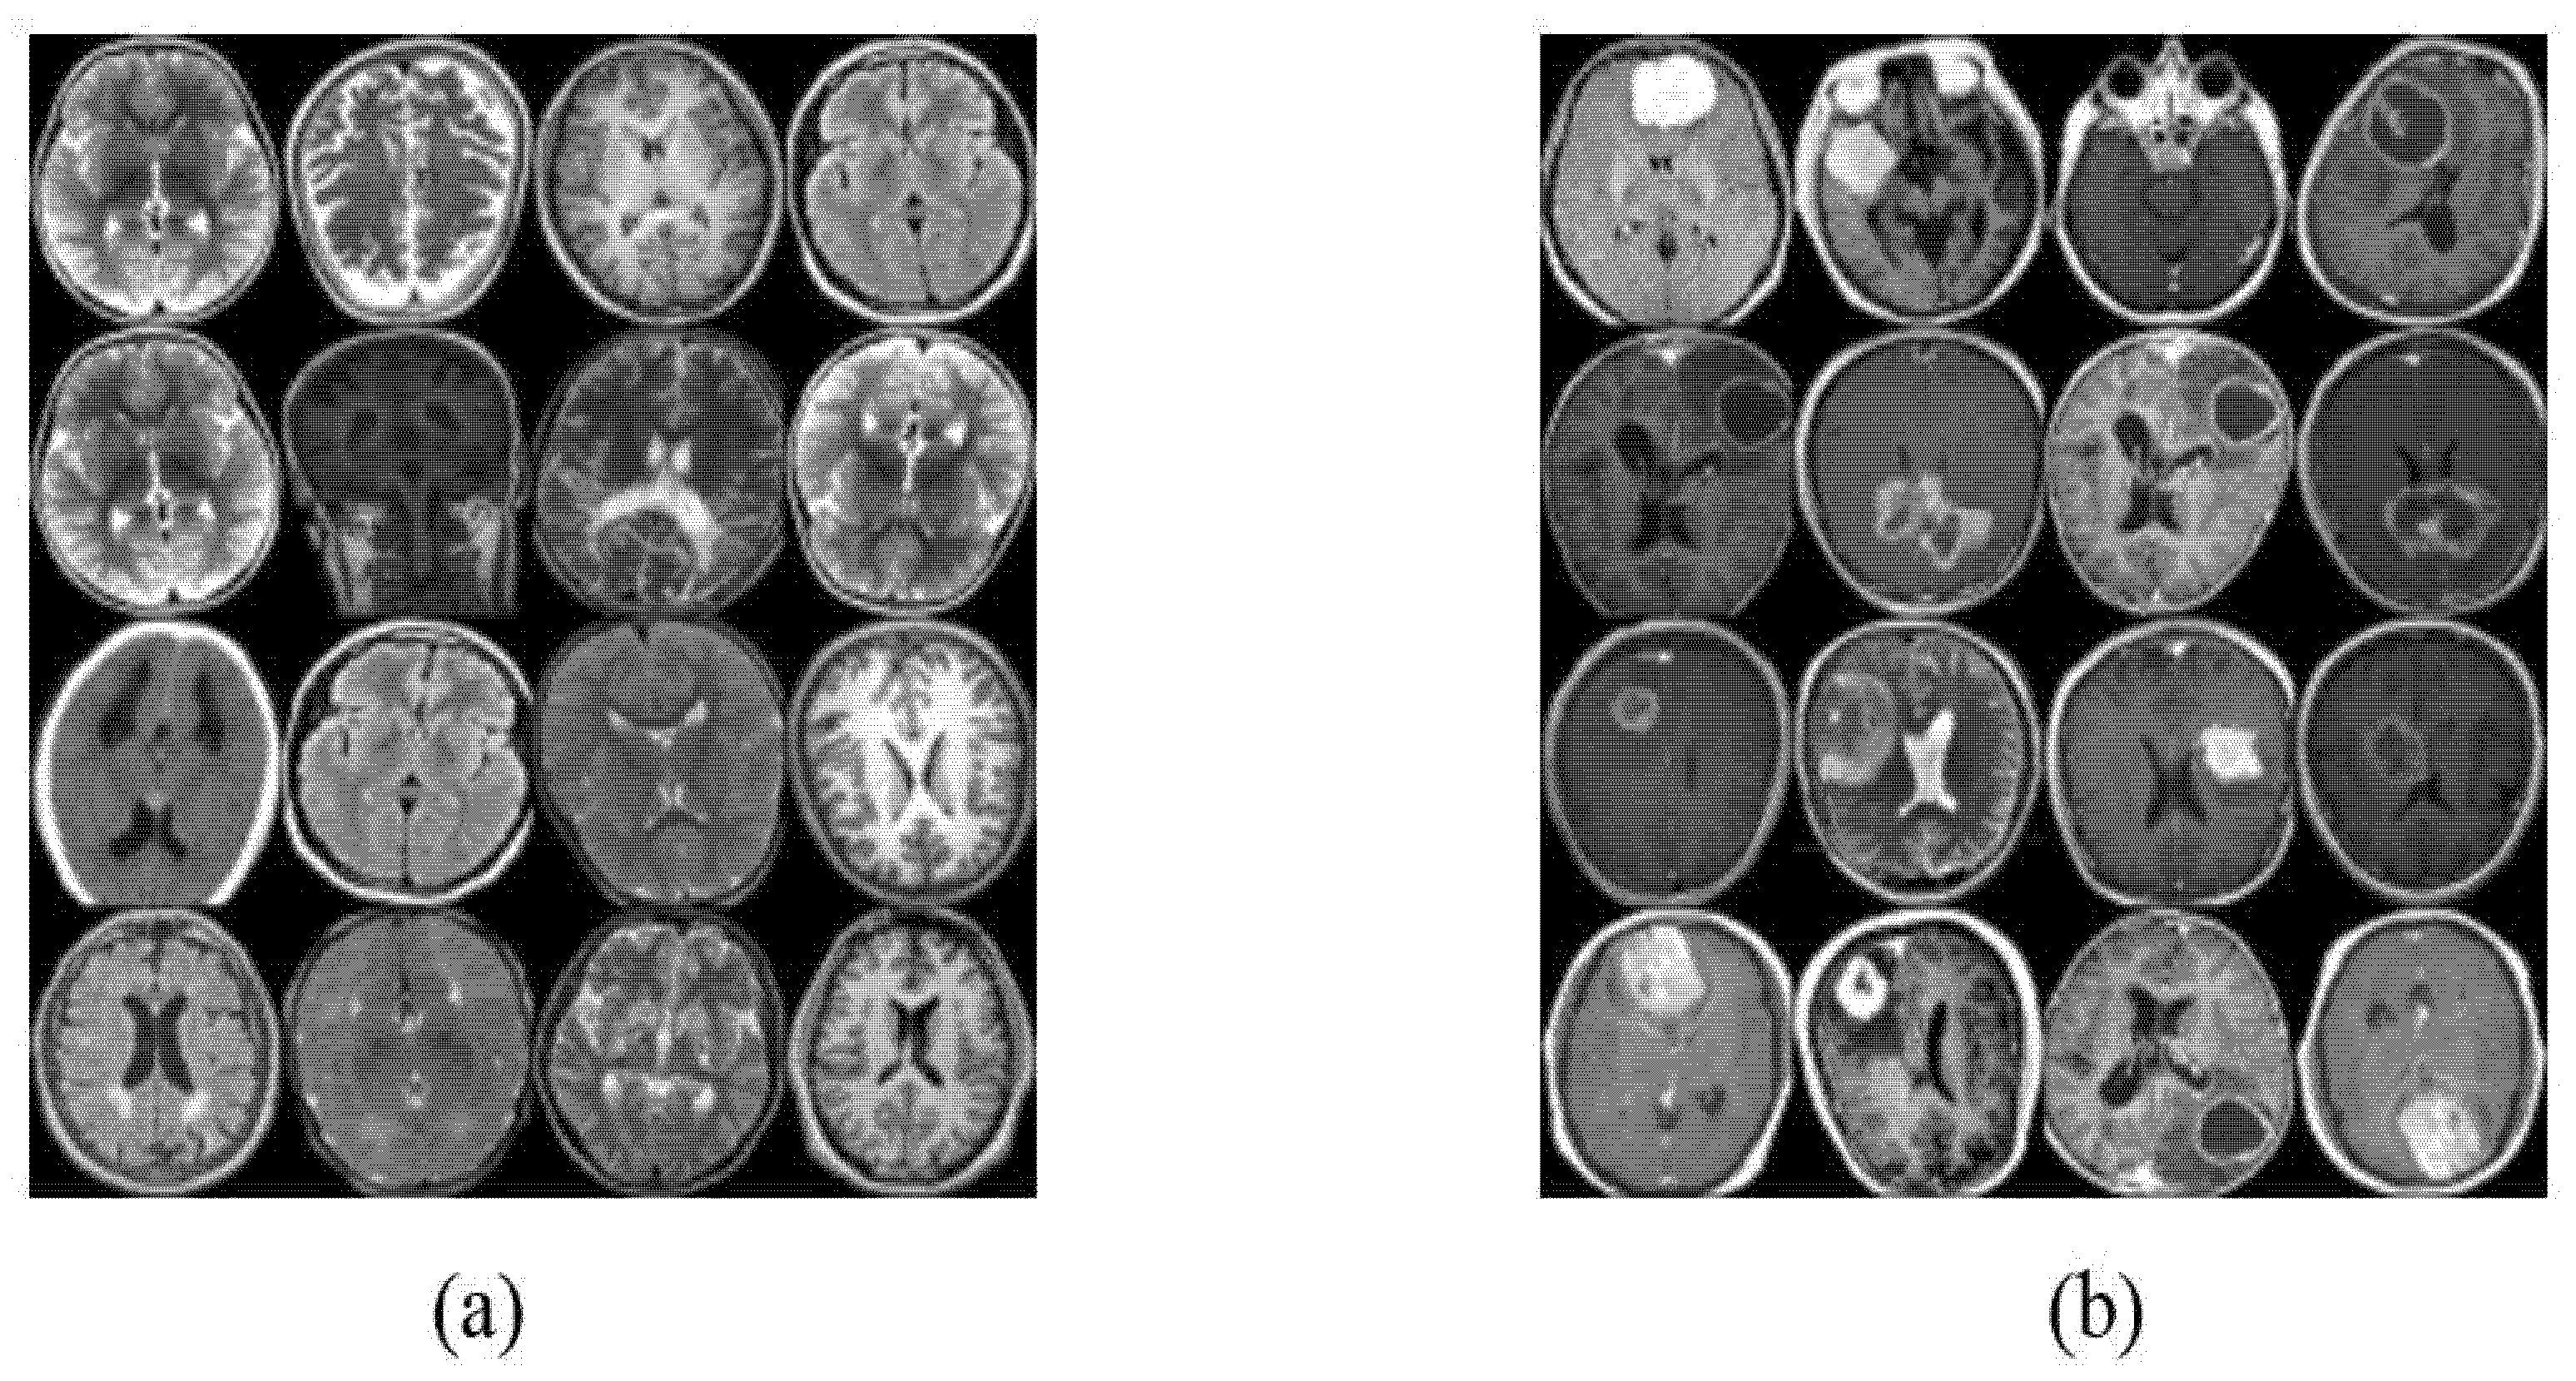

4.1. Datasets of the Study

4.2. Image Augmentation Using Vanilla GAN and DCGAN